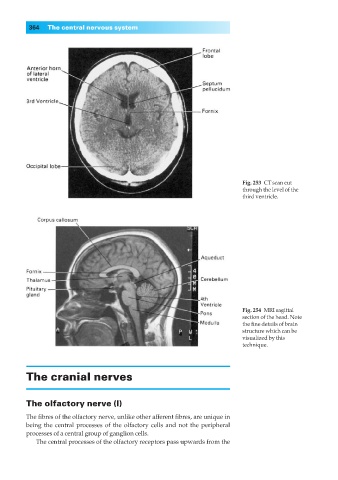

Fig. 253◊CT scan cut

through the level of the

third ventricle.

Fig. 254◊MRI sagittal

section of the head. Note

the fine details of brain

structure which can be

visualized by this

technique.